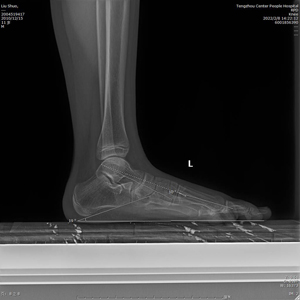

近日,我院足踝外科在潘維亮主任的帶領(lǐng)下,在手術(shù)室和麻醉科的配合下,成功開展青少年扁平足距下關(guān)節(jié)制動術(shù)?;颊呱倌昴行?,11歲,因左足弓塌陷并內(nèi)側(cè)疼痛不適1年收入院。張亞州、范明生主治醫(yī)師為患者完善術(shù)前檢查,嚴格術(shù)前查體,診斷為左足平足癥并左足副舟骨痛。術(shù)前X線示:左足平足并副舟骨?;颊呓?jīng)過足跟墊等保守治療